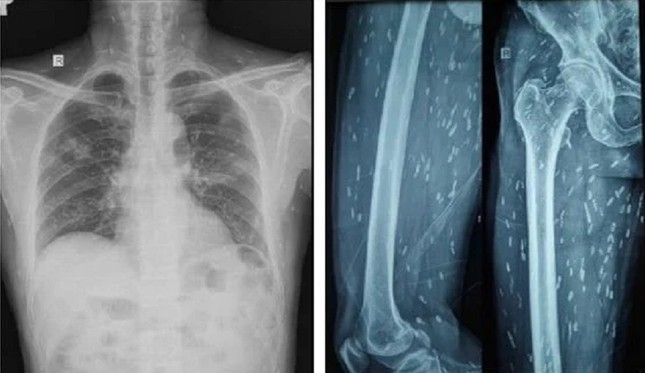

Trên kết quả X-quang và CT-Scan toàn thân, bác sĩ phát hiện bệnh nhân có vô số nang sán dải còn sống hoặc đã bị vôi hóa ở não, nhu mô phổi, trong da, cơ trên toàn bộ cơ thể. Qua điều tra dịch tễ, bác sĩ ghi nhận bệnh nhân có thói quen hay ăn gỏi thịt lợn tái sống và uống nước không đun sôi trong nhiều năm.

Ấu trùng nang sán dải lợn ký sinh khắp cơ thể người bệnh được phát hiện trên kết quả kiểm tra hình ảnh